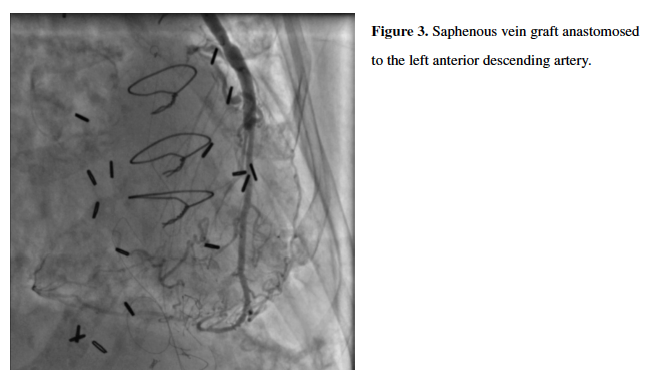

She subsequently underwent further testing, including computed tomography (CTA) of her aortic root and bilateral iliofemoral arteries (aortic valve annulus, 369 mm2; 69 mm perimeter; 20.6 mm diameter; bilateral common iliac arteries with 5 mm mean luminal diameters), three-dimensional transesophageal echocardiography, and cardiac catheterization. Invasive coronary angiography revealed unchanged chronically occluded LAD, LCX, and RCA, and patent SVGs to the distal LAD and OM (Figures 3 and 4). Notably, the RIMA and LIMA grafts were somewhat atretic, but patent and with normal antegrade flow to the anterior and lateral LV myocardium, respectively (Figures 5 and 6), despite competitive filling from patent SVGs.